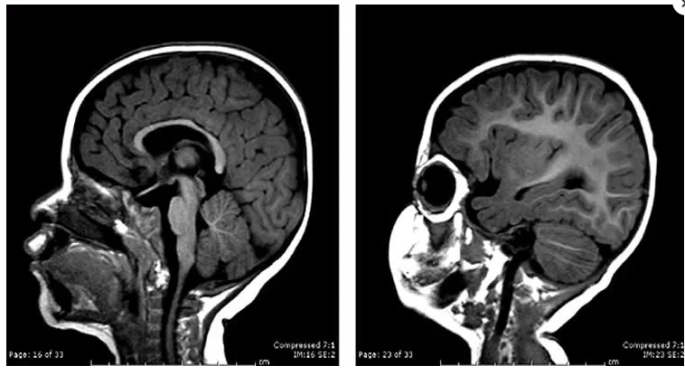

Figura 1Imagem de ressonância magnética de um encéfalo de um recém-nascido com encéfalo com tamanho esperado (esquerda) e de um com microcefalia (direita).

Microcefalia é uma condição congênita rara. Nela, o cérebro e o crânio são menores do que o esperado para a idade do feto ou do bebê. Ela é causada por uma alteração genética ou por substâncias tóxicas como drogas ou radiação ou infecções que interferem no desenvolvimento cerebral. Essa diminuição do cérebro pode causar uma série de déficits neurológicos, cognitivos e motores, e retardo mental. Em Agosto deste ano, a Neuropediatra brasileira  Vanessa Van der Linden Mota percebeu um aumento de vinte vezes no número de casos de microcefalia e alertou colegas e a Secretaria de Saúde. A investigação dela começou por causa de um caso de gêmeos em que um dos bebês nasceu normal e o outro com sequelas de uma infecção grave transmitida pela mãe. Foram feitos exames para citomegalovírus, sífilis, toxoplasmose e rubéola, que costumam ser responsáveis por alguns dos casos de microcefalia, porém todos foram negativos. A prova da relação entre o vírus zika e a epidemia de microcefalia foi descoberta quando a obstetra Adriana Meloa colheu o líquido amniótico de duas pacientes que estavam grávidas de bebês com microcefalia e nele foi encontrado o material genético do zika vírus. Além disso, havia zika vírus no sangue de um bebê do Ceará com microcefalia que acabou morrendo. Assim descobriu-se que a epidemia brasileira de microcefalia está ligada a infecção do zika vírus na mãe, o que já foi  inclusive confirmado pelo Ministério da Saúde e Organização Mundial de Saúde no dia 28 de novembro. Agora está sendo investigada uma possível relação do zika vírus com a síndrome de Guillain-Barré, uma doença neurológica.